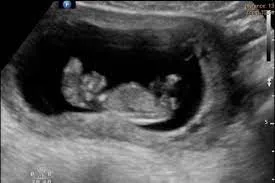

- 超音波finding(第一孕期)

羊水混濁(increased echogenecity of amniotic fluid):在羊水裡消失的腦組織造成的,也會有羊水過多的現象

Mickey mouse sign:雙葉型的腦組織

Beret sign:裸露的腦組織因為無顱骨的包覆,往前突出,可區分exencephaly與anencephaly

頭臀徑會比預期的週數還要小

可使用陰道超音波確認顱骨及腦部的異常